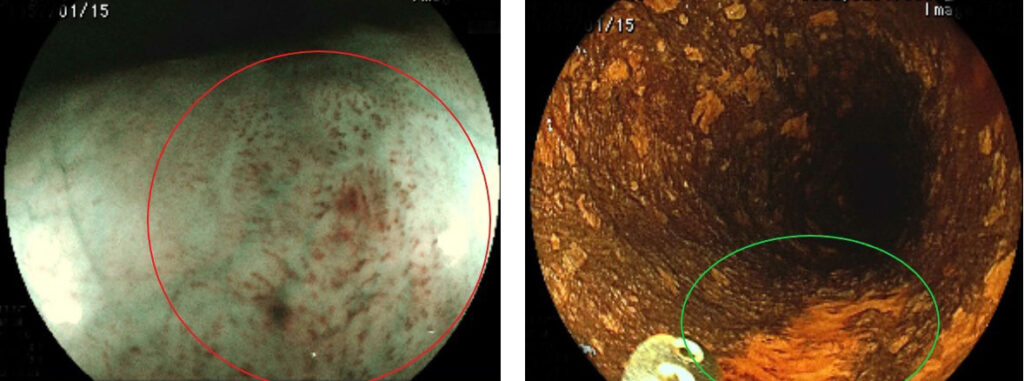

表在型(早期)食道癌の観察例

右:IEE(画像協調画像:BLI image)での観察 病変部分がbrownish area(周囲よりも茶色)で認識されます

右:色素(ルゴール)散布後 正常粘膜は黒く染色されますが病変の部分は染色されず、明るく(オレンジ色に)観察されます